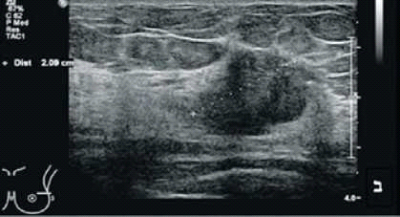

ביופסיות אלו צריכות להיות מדויקות ומוכוונות מטרה. ניתן לבצע את הביופסיה בהכוונת MRI, אך פרוצדורה זו פחות נוחה למטופלת, זמינותה מוגבלת ועלותה גבוהה למדי. על כן, בשלב ראשון לאחר זיהוי ממצא חשוד בבדיקת MRI, יש לזמן את הנבדקת חזרה לבדיקת ממוגרפיה ואולטרסאונד שדיים - בדיקות ממוקדות לאזור החשוד. הסיכוי למצוא את מוקד הממצא שנראה בבדיקת MRI בבדיקה חוזרת של אולטרסאונד ממוקד נע בין 50% ל-70% כתלות בסוג הממצא ב-MRI, גם במקרים בהם בוצעה בדיקת אולטרסאונד זמן קצר קודם לכן שלא הדגימה ממצא חשוד כלשהו[9].

אם הממצא החשוד תואם גם בבדיקת אולטרסאונד, ניתן לבצע ביופסיה מונחית אולטרסאונד להערכת טיבו. ביופסיות אלו נוחות יותר עבור המטופלת, הן זמינות וזולות יחסית ועל כן עדיפות על פני ביופסיה בהכוונת MRI. קיימת חשיבות רבה לתאום בין בדיקת MRI לבדיקת האולטרסאונד על מנת לוודא שהביופסיה אכן דוגמת את הממצא שהיה חשוד בבדיקת MRI. אולם, היות שבדיקת MRI רגישה יותר מממוגרפיה או אולטרסאונד, 30-50% מהממצאים החשודים יודגמו רק בבדיקת MRI. לממצאים אלו תבוצע ביופסיה מונחית MRI.